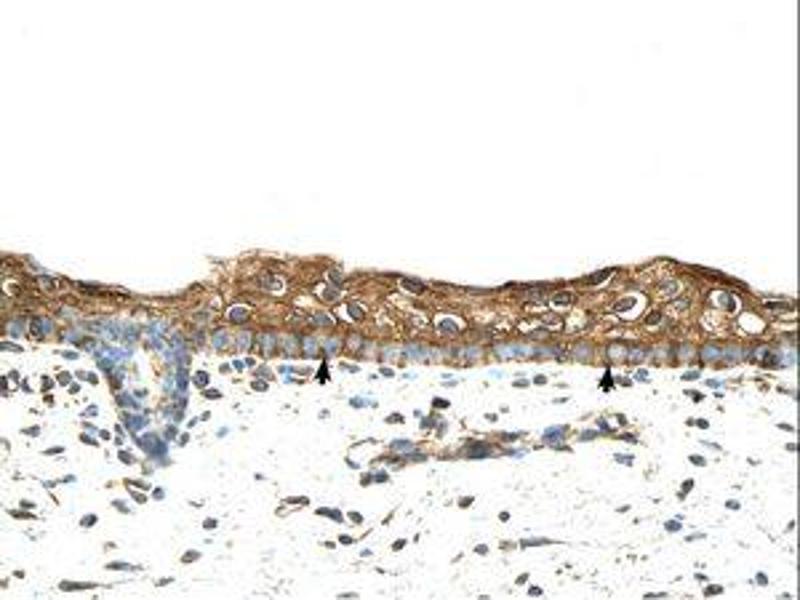

Cet anticorps anti-RBPMS Polyclonal Lapin (ABIN320529) détecte spécifiquement RBPMS dans WB, IHC et IHC (p). L’anticorps est réactif avec des échantillons de Humain, Rat, Souris, Chien, Boeuf (Vache), Cobaye, Cheval, Lapin, Singe, Roussette (Chauve-souris), Poulet, Porc et Xenopus laevis.

Western Blotting (WB), Immunohistochemistry (IHC), Immunohistochemistry (Paraffin-embedded Sections) (IHC (p))

Approved: IHC, IHC-P, WB